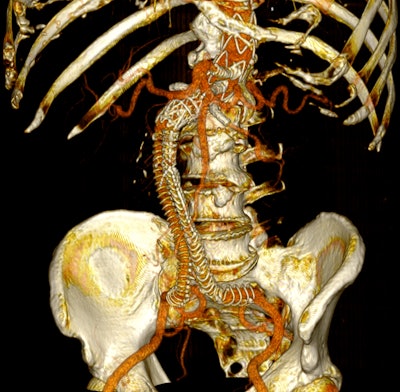

Postoperative 3D volume rendering of the fenestrated endograft reconstruction: 3D volume-rendered reconstruction obtained in Horos using the standard soft-tissue preset. The image displays the postoperative appearance of the fenestrated endograft and visceral stents, extending from the descending thoracic aorta to the iliac bifurcation, acquired during the follow-up CT angiogram one month after the procedure. The reconstruction shows patent visceral branches with well-perfused stents, absence of endoleak, and successful restoration of the previously disconnected left limb with adequate iliac perfusion.Dr. Juan Carlos Gomez-Rodriguez et al and Cureus